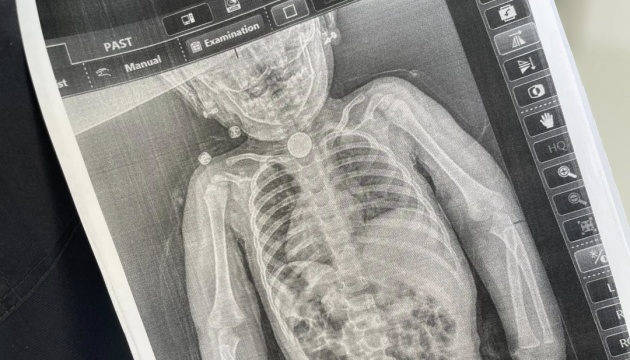

На початку весни батьки знову повезли дочку до лікарні та наполягли на додатковому обстеженні. Дівчинці зробили рентген, який чітко показав стороннє тіло у стравоході. А під час ендоскопічного обстеження вдалося встановити, що у ділянці першого фізіологічного звуження стравоходу міцно застрягла кругла літієва батарейка діаметром 2,5 см. Навколо неї сформувалися набряк та гіпергрануляції слизової оболонки — ознаки тривалого ушкодження тканин.